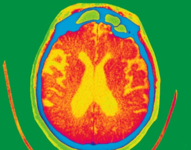

痴呆是由多种疾病所致的临床综合征,最常见的是老年性痴呆即阿尔茨海默病(AD),占所有痴呆的60%左右,长期以来一直是痴呆研究的重点。纵观2014年,AD研究领域尤其是其临床诊疗和预防方面取得不少进展,本文回顾如下。

随着人口老龄化的发展,作为全球人口第一大国,我国已进入了不可逆转的老龄化社会,阿尔茨海默病(alzheimer’sdisease,AD)作为威胁老年人身心健康的一大杀手,已经成为世界人民的“公敌”。